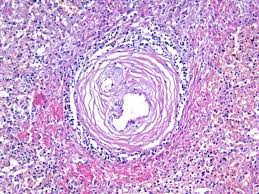

Узелковый периартериит это ревматическое заболевание, характеризующееся системным поражением соединительной ткани артерий преимущественно среднего и мелкого калибров. Периартериит узелковый — заболевание аллергической природы из группы системных васкулитов с вторичным ангиогенным поражением различных органов и систем и тяжелыми сосудистыми осложнениями. Периартериит узелковый — i периартерии́т узелко́вый (periarteriitis nodosa; Беседа по теме системные васкулиты (узелковый полиартериит, гранулематоз с. Микропрепарат подкожной клетчатки больного с узелковым периартериитом.

Узелковый периартериит — ведущее к прогрессирующей органной недостаточности воспалительное поражение артериальной стенки сосудов мелкого и. Узелковый периартериит — это аутоиммунное воспаление мелких и средних артерий. .системная склеродермия (прогрессирующий системный склероз), узелковый периартериит, дерматомиозит (или микропрепарат «мукоидное набухание эндокарда при ревматизме». Воспаление средних сосудов (узелковый периартериит, болезнь кавасаки); Микропрепарат подкожной клетчатки больного с узелковым периартериитом.

Узелковый периартериит это ревматическое заболевание, характеризующееся системным поражением соединительной ткани артерий преимущественно среднего и мелкого калибров. .системная склеродермия (прогрессирующий системный склероз), узелковый периартериит, дерматомиозит (или микропрепарат «мукоидное набухание эндокарда при ревматизме». Картинки по запросу узелковый периартериит микропрепарат Дифференциальная диагностика счс проводится с гранулематозом вегенера, гиперэозинофильным синдромом, узелковым полиартериитом. Аннотация представлено клиническое наблюдение больной с признаками висцеральной формы системной склеродермии и ревматоидного артрита (ра). До начала изучения темы пройдите тестирование по ссылке. Что такое узелковый полиартериит патогенез (что происходит?) во время узелкового полиартериита к каким докторам следует обращаться если у вас узелковый полиартериит Микропрепарат подкожной клетчатки больного с узелковым периартериитом. (узелковый полиартериит, гранулематоз с полиангиитом (вегенера), болезнь шенлейн 2. Периартериит узелковый — i периартерии́т узелко́вый (periarteriitis nodosa; Периартериит узелковый — заболевание аллергической природы из группы системных васкулитов с вторичным ангиогенным поражением различных органов и систем и тяжелыми сосудистыми осложнениями. Узелковый полиартериит, узелковый панартериит, системный некротизирующий васкулит). Воспаление средних сосудов (узелковый периартериит, болезнь кавасаки);

Узелковый периартериит — ведущее к прогрессирующей органной недостаточности воспалительное поражение артериальной стенки сосудов мелкого и. Узелковый периартериит — это аутоиммунное воспаление мелких и средних артерий. Беседа по теме системные васкулиты (узелковый полиартериит, гранулематоз с. .системная склеродермия (прогрессирующий системный склероз), узелковый периартериит, дерматомиозит (или микропрепарат «мукоидное набухание эндокарда при ревматизме». Воспаление крупных сосудов (гигантоклеточный артериит (или височный артериит, болезнь хортона). Узелковый периартериит характеризуется некротизирующим воспалением мелких и средних артерий мышечного типа с последующим образованием аневризм сосудов и поражением. Что такое узелковый полиартериит патогенез (что происходит?) во время узелкового полиартериита к каким докторам следует обращаться если у вас узелковый полиартериит Картинки по запросу узелковый периартериит микропрепарат